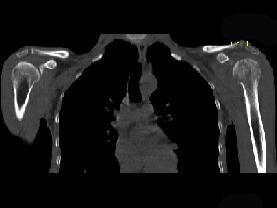

问题 患者,男,29岁,行走时不慎跌倒,曾拟为左肱骨头骨折并行固定,但半年后疼痛未减轻,触压局部骨质松软,如触及乒乓球感,明显叩击痛,请结合所提供图像,选择最佳答案 ( )

选项 A、骨转移瘤 B、骨结核 C、骨网状细胞肉瘤 D、左肱骨头骨折 E、化脓性骨髓炎

答案 C